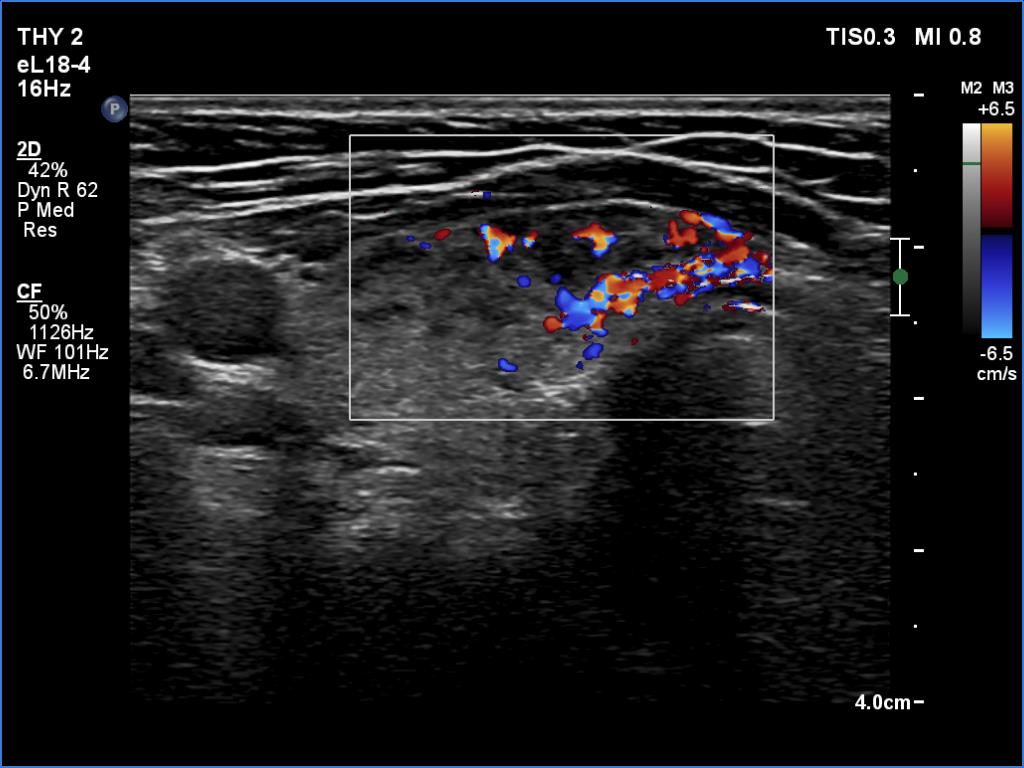

Ultrasonography. The thyroid was echonormal and presented several minimally-moderately hypoechoic areas. One of them, which was located in the central part of the right lobe was deeply hypoechoic and corresponded to pathological nodule. The other lesions seemed to be not true nodules but more active foci of thyroiditis.

Comment. It is worth comparing the deeply hypoechoic nodule with the other discrete lesions. The former has regular, sharp borders, and its echogenicity differs from other areas of the thyroid. These are the main clues of differentiation of a true nodule from a discrete lesion of Hashimoto's thyroiditis.